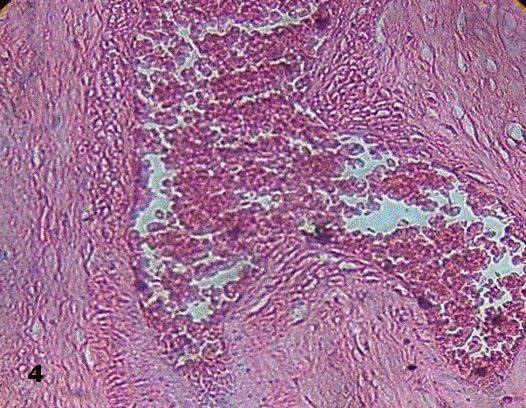

This lumen was obliterated by them in some of the stained sections. Images revealing early formation of thrombus were visualized (Figs. 3, 4).

Fig.4.Changes in the wall of the vessel is observed

associated to stasis of erythrocytes in the lumen of vessel of a stem villi. 100x H&E.

Aneurysmal prolongation of vessel is a consequence of elevated blood pressure that modifies the wall of the vessel as seen in Fig.4.